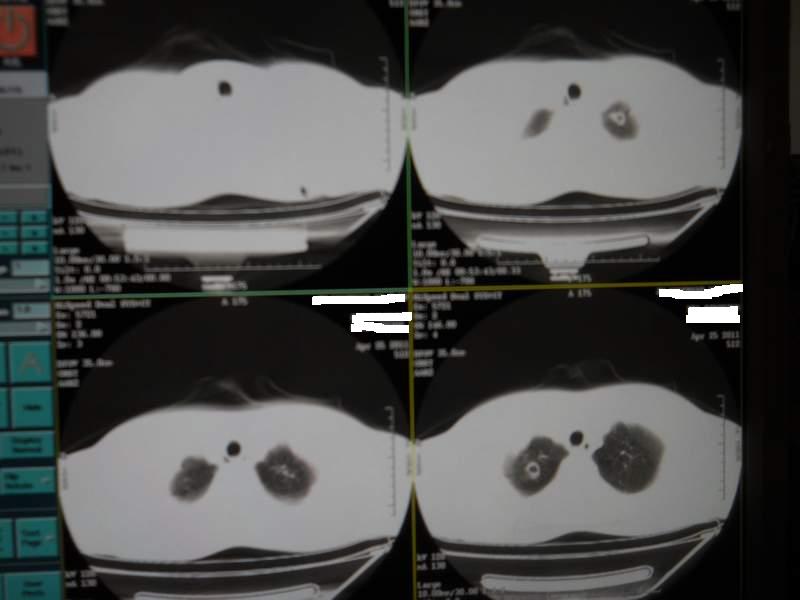

肺霉菌感染

男,22岁,一年前诊断马尔菲尼青霉菌感染,多次复查CT。多次HIV阴性。最近两次CT图片。有实验室结果。

最近实验室检查结果:霉菌感染。